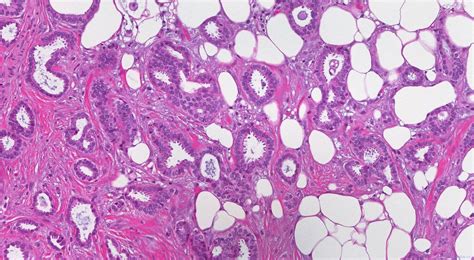

Alright, so what exactly is invasive right breast carcinoma ? Basically, it’s cancer that starts in the right breast and has spread beyond the ducts or lobules where it originated. It’s considered “invasive” because it has broken through the boundaries of the tissue where it began, potentially spreading to other parts of the body. There are various types, with the most common being invasive ductal carcinoma and invasive lobular carcinoma . The former starts in the milk ducts, while the latter begins in the milk-producing lobules. Understanding the type helps doctors determine the best course of treatment. The right breast is simply the location where this process is taking place. This localization is important, as it helps determine the extent of the cancer and guide treatment decisions, like surgery, radiation, and medication. The term “carcinoma” itself refers to a cancer that originates in the epithelial cells – the cells that cover the surfaces of the body, including the breast tissue. This means that when we’re talking about invasive right breast carcinoma , we’re referring to a very specific type of cancer that must be accurately identified and documented for proper care. Guys, remember that early detection is key, and regular screenings are super important. If you feel anything unusual, don’t hesitate to see a doctor! It’s better to be safe than sorry, right?